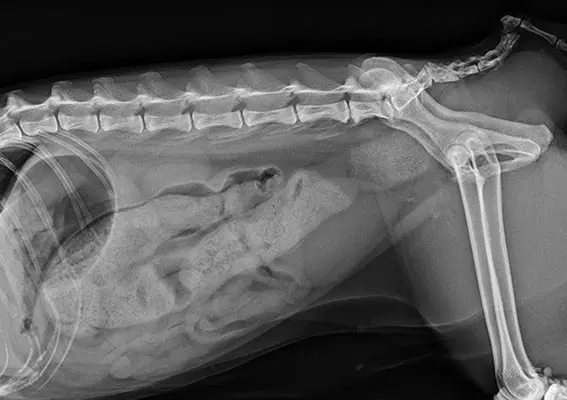

RADIOLOGIA

- Wojciech Atamaniuk , Petra Lowen

- 9 października 2025